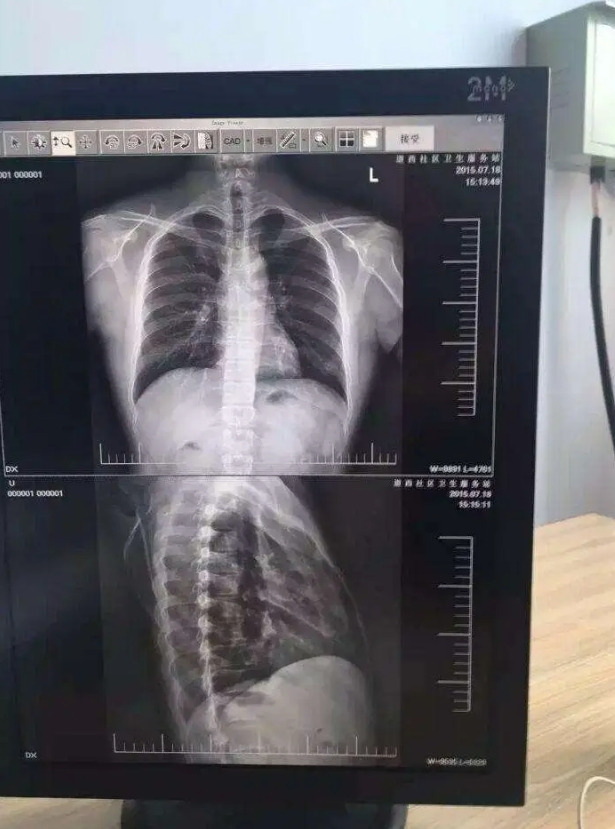

27寸手术室医疗显示器

在现代化手术室中,医疗显示器作为医生观察患者影像信息的关键设备,其性能与质量直接关系到手术的精准度和成功率。其中,27寸手术室医疗显示器凭借其独特的优势,逐渐成为众多医疗机构的首选。本文深圳利豪捷小编将探讨27寸手术室医疗显示器的相关内容,深入解析这款在手术室中发挥着重要作用的医疗设备。

27寸手术室医疗显示器通常具备极高的分辨率,能够呈现出细腻、清晰的影像。在手术过程中,医生需要清晰地观察患者的解剖结构、病变部位以及手术器械的精确位置。高分辨率的显示器可以确保每一个细节都清晰可见,帮助医生做出准确的判断和操作。例如,在神经外科手术中,医生需要精准地避开神经和血管,27寸显示器所呈现的高清影像能够让医生清晰地分辨出这些细微结构,大大提高了手术的安全性;

手术室的光线环境较为复杂,为了确保医生在任何情况下都能清晰地看到影像,27寸医疗显示器具有高亮度和高对比度的特点。高亮度可以保证在明亮的环境下影像依然清晰可见,而高对比度则能够突出影像中的细节,使医生更容易分辨不同的组织和结构。在心脏介入手术中,医生需要在X光影像的引导下进行操作,高亮度和高对比度的显示器能够清晰地显示血管和导丝的位置,为手术的顺利进行提供有力支持。